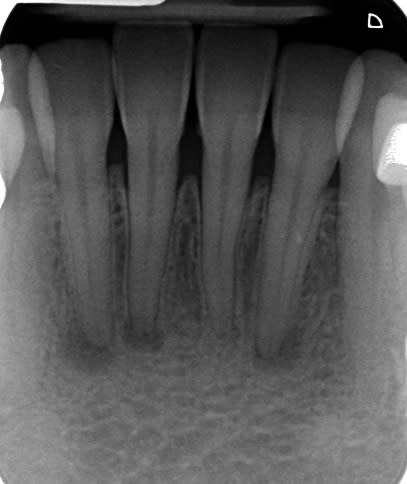

Je reçois la patiente dont la radio figure ci-dessous, 37 ans, pour un motif qui n'a rien à voir avec ce qui nous occupe.

Les tests de vitalité sont aussi normaux qu'ils peuvent l'être, les dents sont asymptomatiques, elle a un antécédent de trauma facial/dentaire dans sa jeunesse (il y a plus de 20 ans), et a eu de l'odf à l'adolescence. RAS depuis.

Enfin cinquièmement sur une dent avec des canaux larges comme on le voit à la radio , il est clair que le traumatisme est l’origine de ces lésions. Aucune autre cause ne peut expliquer cette nécrose.

La lumière canalaire est présente donc la dent ne se protège pas.

Je ne l'ai pas précisé, mais la patiente présente le même type d'image sur la 36, porteuse d'un ancien composite parfaitement étanche à première vue, quoiqu'un peu profond.

Réactive au froid également.

En temps normal, je serais assez d'accord avec toi; mais là il n'y a aucune dyschromie, la réponse au froid n'est même pas un peu modifiée, et si les lésions dataient de 20 ans, elles seraient plus volumineuses.

D'ailleurs, si les dents étaient nécrosées depuis 20 ans, on aurait une différence de lumière canalaire avec la 31 restée vivante.